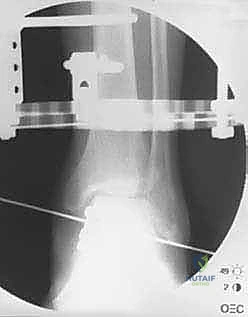

الخطوة الثانية: تركيب الإطار الخارجي (Ilizarov Frame)

هذه هي المرحلة الهندسية الدقيقة. يتم تركيب حلقتين معدنيتين حول عظمة الساق (Tibia) وحلقة ثالثة حول القدم (تثبت في عظمة العقب Talus وعظام مشط القدم).

الخطوة الثالثة: إدخال الأسلاك والمسامير (Wire and Pin Placement)

يتم تمرير أسلاك معدنية رفيعة جداً (Kirschner wires) ومسامير نصفية (Half-pins) عبر العظام لتثبيت الحلقات. يعتمد الأستاذ الدكتور محمد هطيف على معرفته التشريحية العميقة واستخدام جهاز الأشعة المرئي (C-arm) لضمان مرور هذه الأسلاك في "الممرات الآمنة" (Safe corridors) بعيداً عن الشرايين والأعصاب الحيوية.

الخطوة الرابعة: تركيب المفاصل الصناعية (Hinges)

هنا يكمن السر الأكبر للنجاح. يتم توصيل حلقة الساق بحلقة القدم باستخدام مفاصل معدنية قابلة للحركة (Hinges). يجب أن يتم وضع محور هذه المفاصل المعدنية ليتطابق تماماً مع المحور التشريحي الطبيعي لدوران مفصل الكاحل (Center of Rotation of the Talus). هذه الدقة تضمن إمكانية تحريك الكاحل أثناء فترة العلاج دون إحداث ضغط غير متساوٍ على الغضروف.

الخطوة الخامسة: تطبيق التشتيت (Distraction)

أثناء العملية، يقوم الدكتور هطيف بإبعاد حلقة الساق عن حلقة القدم تدريجياً وببطء باستخدام قضبان ملولبة، حتى يصل إلى مسافة تشتيت تبلغ حوالي 5 إلى 6 ملليمترات. يتم التأكد من هذه المسافة عبر الأشعة السينية داخل غرفة العمليات.